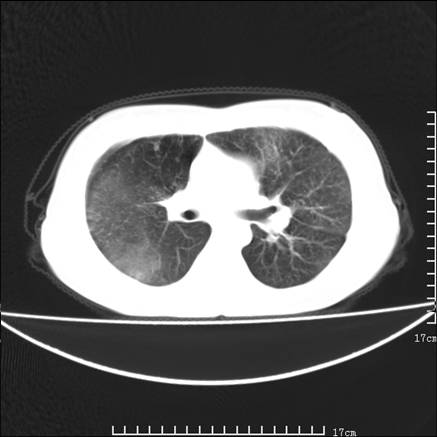

女,46岁,患胃溃疡多年,溃疡大小约1.0cm左右,后于5年前手术,病理为胃癌。主诉:半月前感冒后胸闷,气短,有咳嗽,无明显咳痰,无发热。偶有腰背部不适。

以下为高分辨扫描图像

双肺小叶间增厚,双肺散布粟米影和磨玻璃状影,以双肺上叶为重。结合病史考虑转移(癌性淋巴细管炎)可能性大。

究竟是不是癌性淋巴管炎,抗炎治疗后复查就会明了,抗炎治疗癌性淋巴管炎是不会改善的.个人感觉叶间裂虽然增厚,但比较光滑,符合炎性改变!

支持 肺间质性肺炎,不除外癌性淋巴管炎,建议抗炎治疗复查---------小叶间隔增厚,磨玻璃影及片絮状影

多考虑双肺炎症,建议抗炎治疗后复查,以除外肺癌性淋巴管炎的可能。